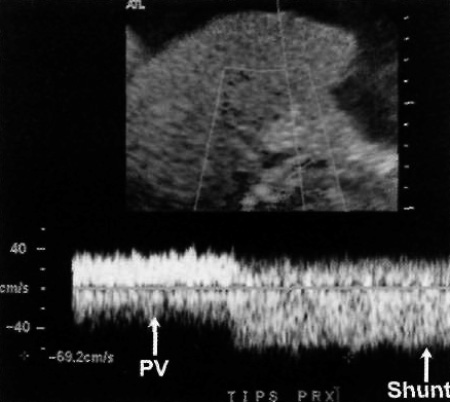

Чтобы избежать получения аномально медленного сигнала в проксимальном конце шунта, курсор нужно расположить достаточно глубоко внутри шунта и как можно дальше от воротной вены. При спектральной допплерографии это положение позволяет определить только типичный кровоток по шунту, а не кровоток воротной вены (фото 11).

Фото 11. Проксимальная скорость по трансъюгулярному внутрипеченочному портосистемному шунту. Фиксируется допплеровский сигнал из проксимального окончания TIPS. Следует обратить внимание на изменение (увеличение) скорости кровотока по мере перемещения курсора от ствола воротной вены вглубь шунта